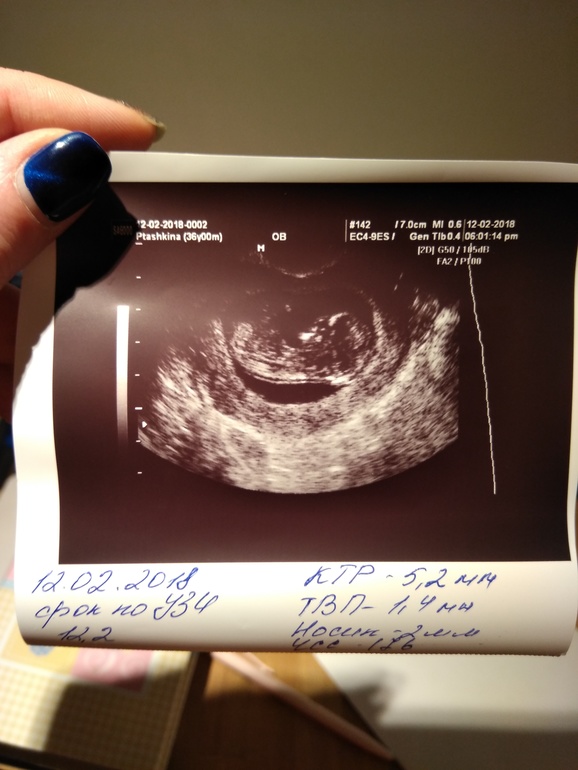

12.02.18 - перед первым скринингом решила сходить на УЗИ. Пошла в 11недель и 3 дня, по УЗИ мы опять опережаем, 12 и 2)) итак: КТР 52мм, твп1,4мм, носовая кость 2мм, чсс176 . Сказали хороший здоровый малыш))) пол пока не известен. Официальный скрининг 16.02 ровно в 12 недель. Интересно расскажут что то или нет?